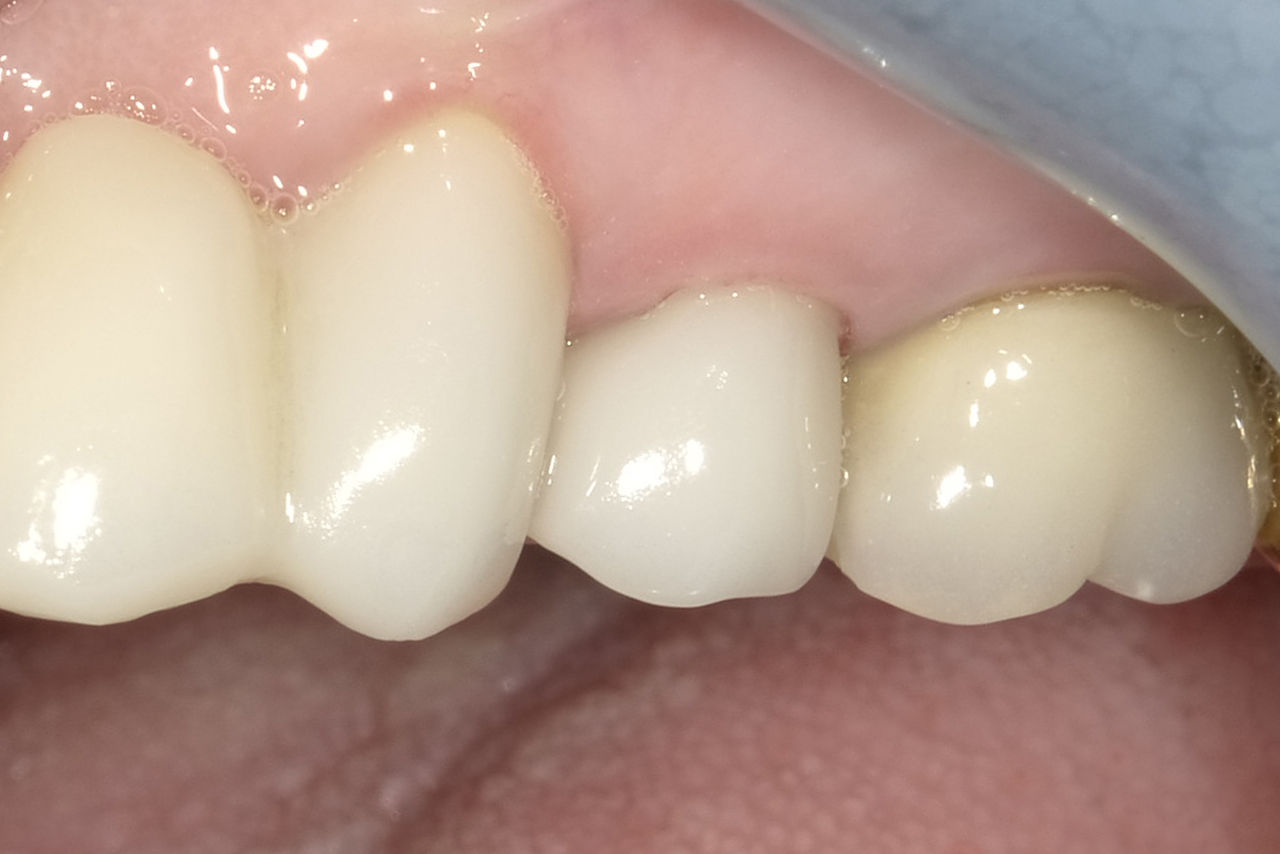

Before

Fractured ceramic restoration made from a leucite-reinforced glass-ceramic after a clinical service time of 12 years.

After

Chairside-fabricated restoration made from an advanced lithium-disilicate ceramic CEREC Tessera.